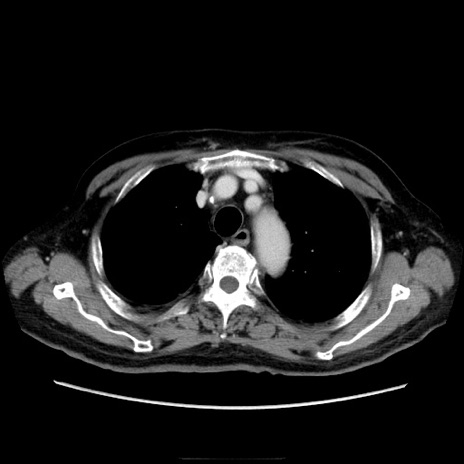

症例21(横断像)

【症例】70歳代男性

【主訴】腹痛

【現病歴】肝硬変・肝細胞癌にてかかりつけの方。約9時間前に食後より腹痛出現。症状が徐々に増悪し、嘔吐出現したため来院。

【既往歴】肝硬変、肝細胞癌(RFA、TACE後)

【身体所見】意識清明、表情苦悶様、BT 36℃、BP 129/78mmHg、P 88bpm、SpO2 97%(RA)、右上腹部から心窩部にかけて圧痛あり、反跳痛なし、筋性防御あり。

【データ】WBC 5800、CRP 0.16